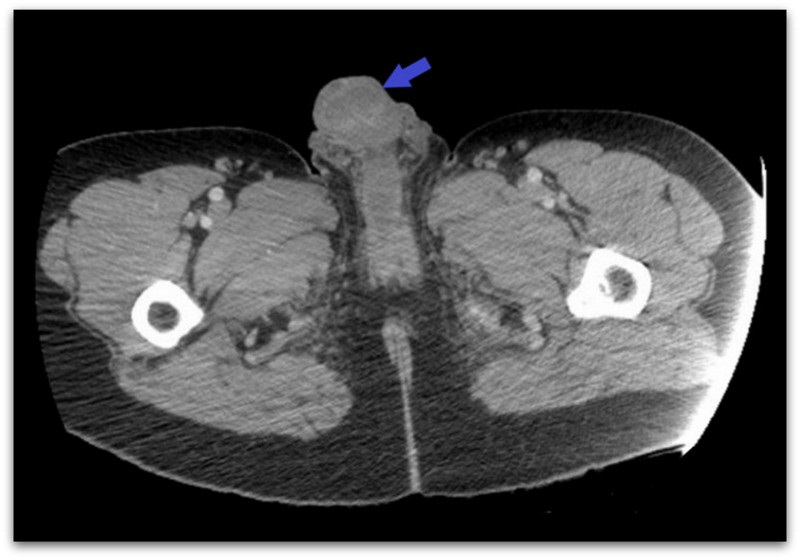

Лекарите од Bronx, во New York, откриле дека кожата на пенисот на непознат маж умрела, поцрнела и од која истекувал секрет со непријатен мирис. Кожата околу неговиот скротум, исто така, почнал да гние и да се лупи од коренот на неговиот пенис.

Пациентот признал дека инјектирал кокаин во дорзална вена која се протега по должина на врвот на пенисот, иако не кажал зошто.

По приемањет, пациентот рекол дека немал проблем со инјектирање на кокаин во неговиот пенис двапати во текот на претходните две недели.